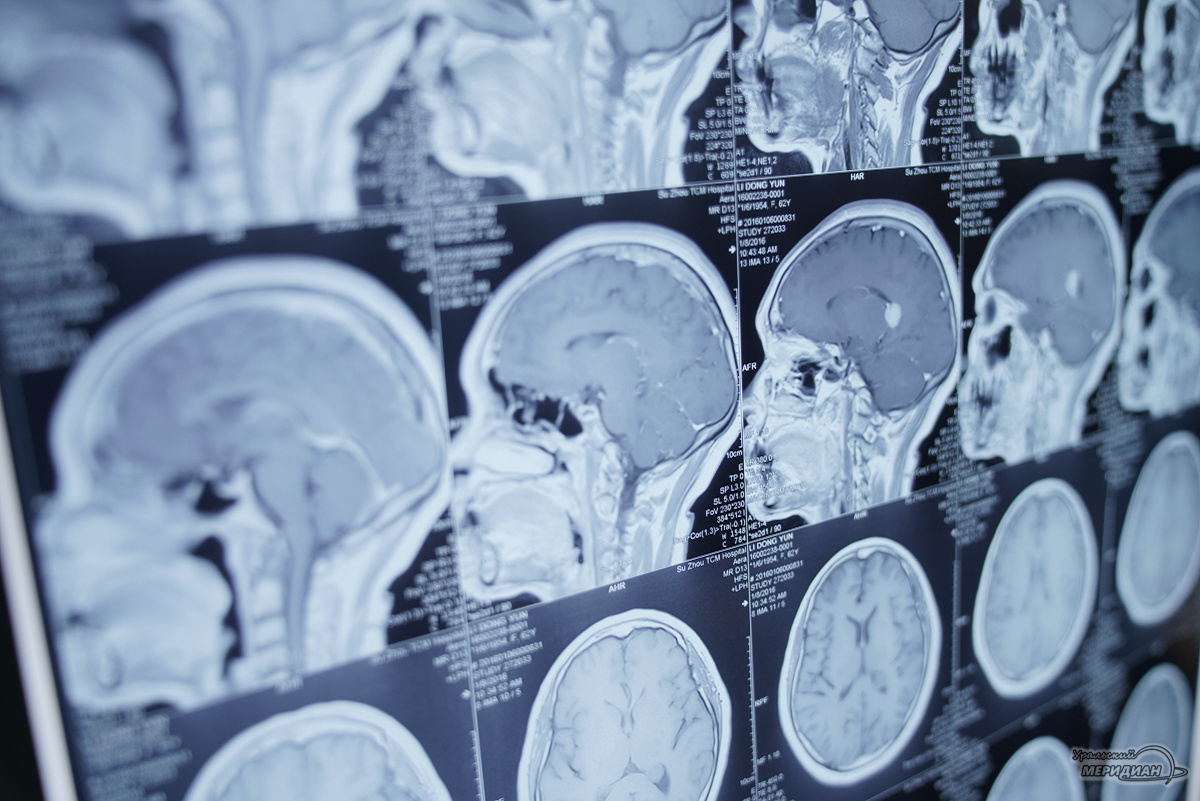

В Серовской городской больнице работает молодое отделение рентгенохирургических методов диагностики и лечения. За полтора года здесь провели более 3 тысяч операций. Удалось предотвратить тысячи инфарктов и инсультов, а также избежать ампутаций у многих пациентов, отметили в минздраве региона. Отделение было открыто в июне 2024 года, и уже в 2025 году врачи выполнили 2057 высокотехнологичных вмешательств, что вдвое больше плановых показателей. Основное внимание уделяется спасению пациентов с сердечно-сосудистыми заболеваниями — проведено 1680 коронарографий (исследований сосудов сердца), 174 операции ангиопластики и стентирования сосудов нижних конечностей и 117 лазерных процедур при варикозе, перечислил руководитель отделения, сосудистый хирург Иван Нарышкин. Особенность нового отделения в том, что теперь современные методы лечения доступны бесплатно по месту жительства, а не только в крупных областных центрах. Все процедуры, включая дорогостоящие ангиографию и стентирование, выполняют

Отделение было открыто в июне 2024 года, и уже в 2025 году врачи выполнили 2057 высокотехнологичных вмешательств, что вдвое больше плановых показателей. Основное внимание уделяется спасению пациентов с сердечно-сосудистыми заболеваниями — проведено 1680 коронарографий (исследований сосудов сердца), 174 операции ангиопластики и стентирования сосудов нижних конечностей и 117 лазерных процедур при варикозе, перечислил руководитель отделения, сосудистый хирург Иван Нарышкин.